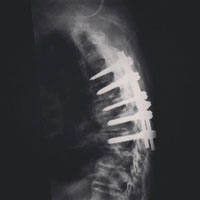

We shall see: On November 10th, 2014 a motorcycle accident left my father paralyzed and lying in a South African hospital bed. I put my life on hold so I could go and help him fight for his.

Making these photos have helped me cope and has saved me the heavy task of having to explain just how awful this is. It's all there on Instagram for the world to see. I don't need to explain it to my friends when I get home or make excuses for leaving my life behind.

He encourages me to keep shooting and to publish this work. Photography has always been a shared interest between us — after all it was him who gave me my first decent camera.

These past few months have brought us closer than ever before. The grief and stress has exposed a vulnerable and loving side of him that I always knew existed, but never thought I'd see. His health remains precarious and his care is ongoing. It is impossible to know what our lives will look like in a year. When friends and family ask, I always say the same thing: We shall see.